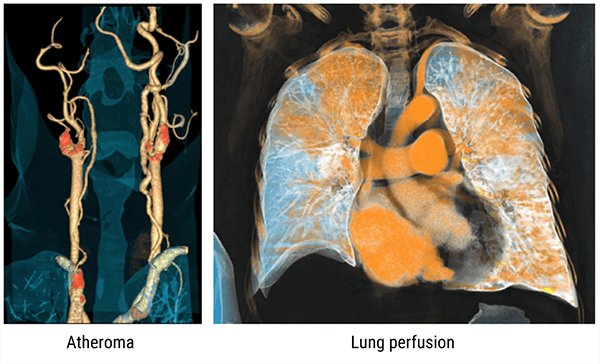

Examples

The below images show 3D scanning using the dual-energy technology.

Additional examples highlighting articular gout as well as a pulmonary nodule using dual-energy technology.